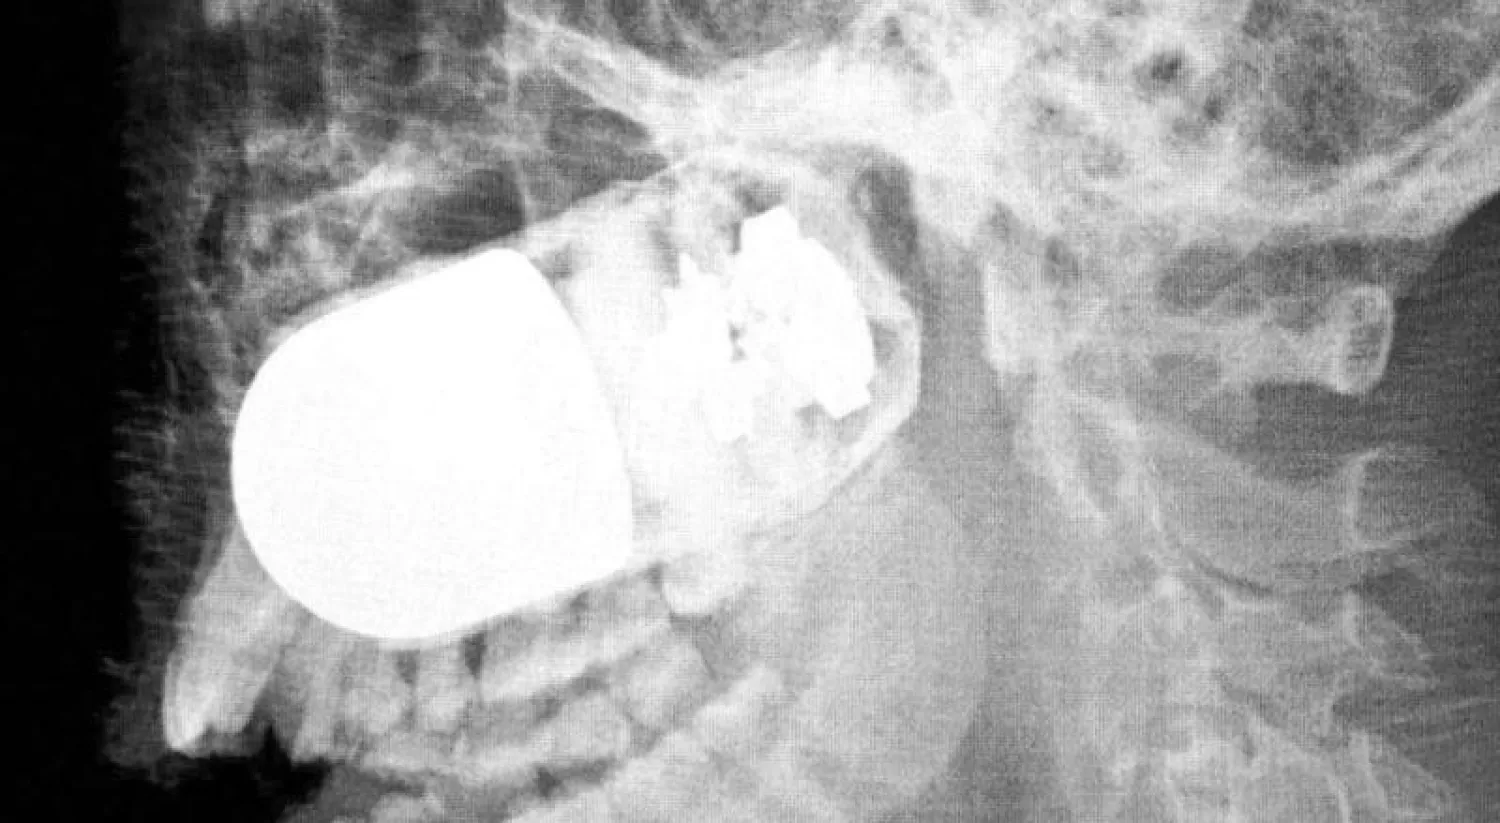

صورة الأشعة التي تظهر وجود القنبلة (إ.ب.أ)